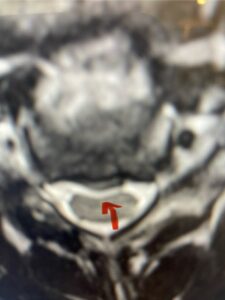

Another patient, a 77 year-old female, presents with pain, numbness, and weakness of her arms and difficulty with balance over a 6-month period. MRI revealed severe osteophytic disease at C5-C7 with cord compression (Fig. 4). Further work-up by fine-cut cervical CT to evaluate the nature of compression revealed a completely calcified osteophyte (Fig. 5). Although the patient had a good lordosis and a posterior cervical approach would accomplish an adequate decompression, we elected to perform a two-level anterior cervical discectomy and fusion. This particular osteophyte is formidable because of its size but the compression was all anterior and would be a less invasive approach. Fortunately, during the procedure, the patient had a fair amount of osteoporosis which allowed the osteophyte to be drilled and bit away with considerable ease. Interestingly, the C6 7 osteophyte which was more a sheet of osteophyte was more challenging to remove. In the end the decompression went well, and we placed two interbody devices filled with bone graft with plates at each level (Fig. 6). The patient had a nice recovery with immediate reduction of pain and numbness. This case demonstrates the importance of recognition of cervical myelopathy in its early stages. A significant reversal of function is generally the rule if the patient has appropriate correlative findings on exam and MRI, particularly with long tract distribution weakness development within a year time period.

Figs 4a: Sagittal and axial T2-weighted cervical MRIs demonstrating large osteophyte worse at C5-6 compressing spinal cord more eccentrically to the left (red arrows)